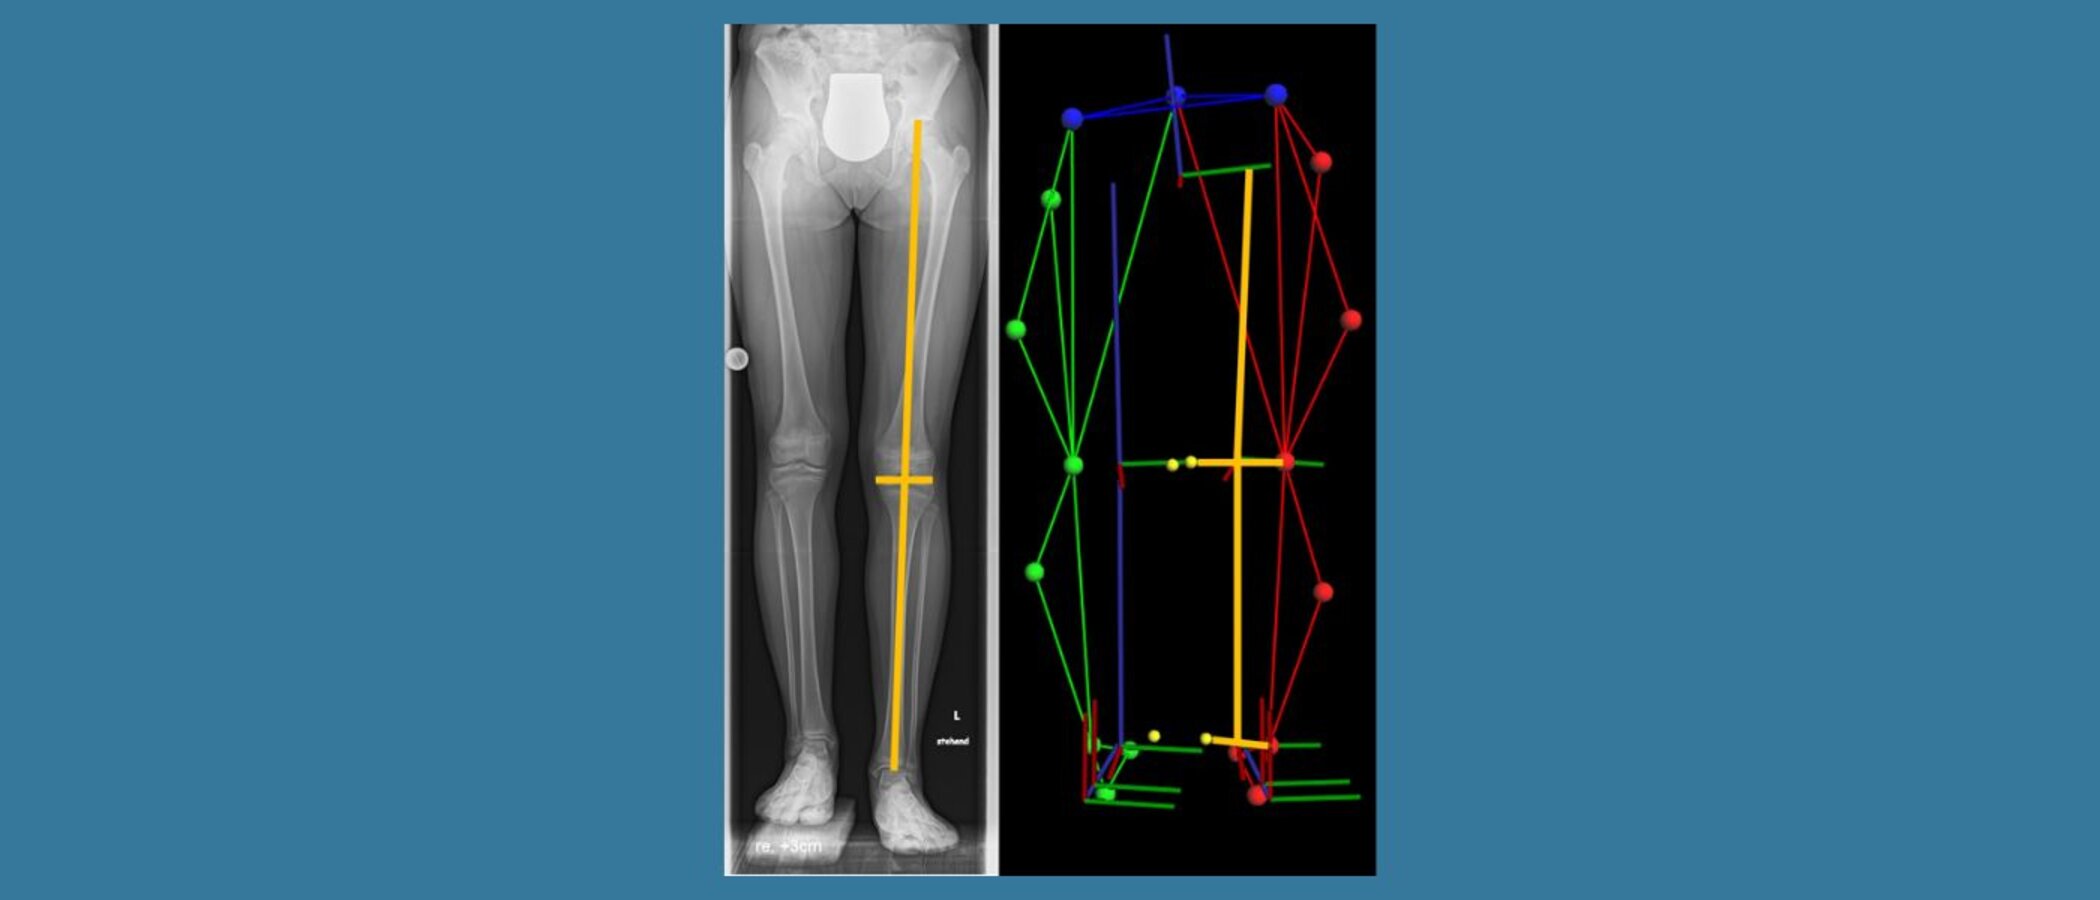

Die Studie untersuchte verschiedene Methoden zur Bestimmung von Beinlängenunterschieden bei Kindern und Jugendlichen. Dabei wurden 31 Patienten mit einem durchschnittlichen Alter von 12,3 Jahren einbezogen, die einen Beinlängenunterschied zwischen 0 und 3,6 cm aufwiesen.

Es wurden zwei Methoden mit dem Goldstandard der Röntgenanalyse verglichen: die herkömmliche Maßbandmessung und eine Methode der instrumentellen Ganganalyse unter Verwendung von Gelenkzentren.

Die Ergebnisse zeigten, dass die Methode mit Gelenkzentren genauer war als die Maßbandmessung. Diese Studie betont die Praktikabilität der Bestimmung von Beinlängendifferenzen mittels instrumenteller 3D-Standanalyse anhand der Distanzen zwischen den Gelenkzentren, die in der klinischen Praxis angewendet werden kann.

Sie unterstreicht auch, dass die 3D-Bewegungserfassung eine genaue und präzise Alternative zur herkömmlichen Maßbandmessung darstellt und dass verschiedene Berechnungsmethoden des Hüftgelenkszentrums die Genauigkeit nicht beeinflussen.